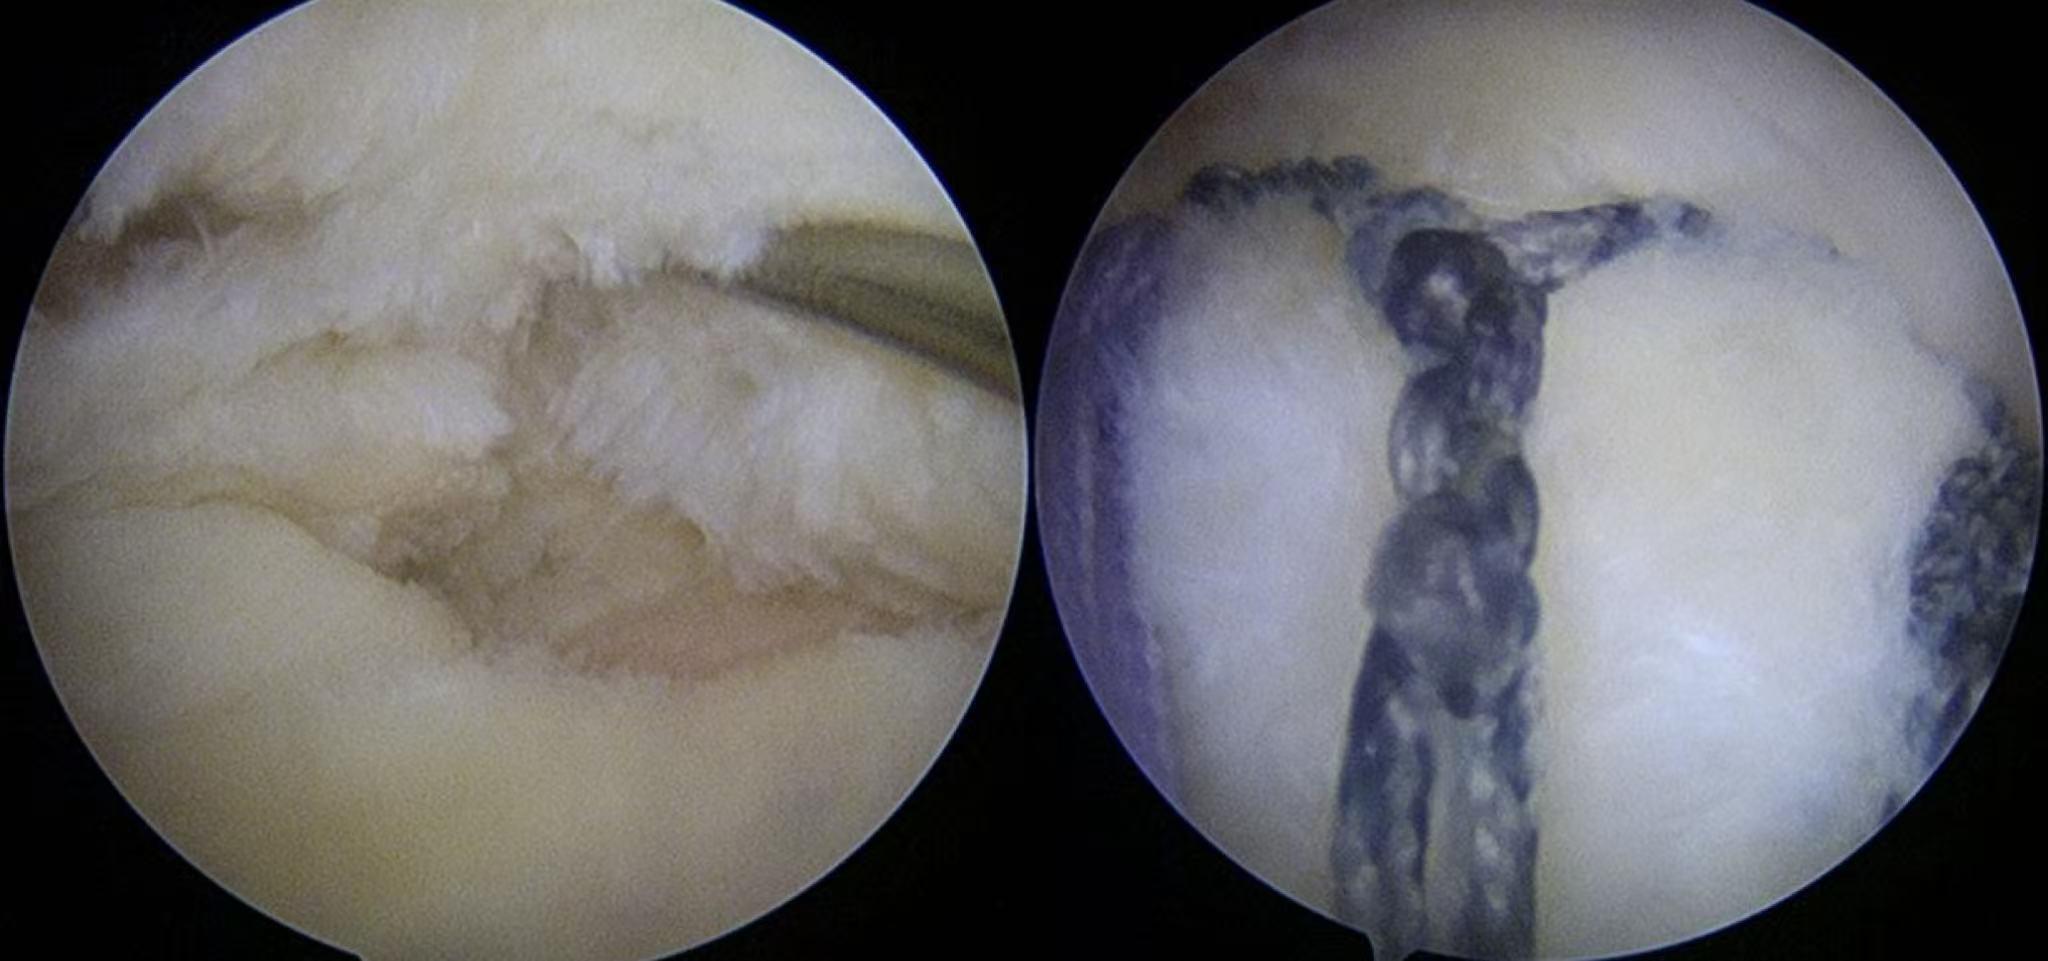

左:肩袖撕裂口;右:Y-Loop技术修复完成后,肌腱恢复覆盖,张力均匀。

然而,对于肩袖损伤患者来说,传统的缝合方式如同几个独立的“扣子”,力量集中在几个点上,对于本身已退变的肌腱,缝线容易产生切割。而Y-Loop技术的核心优势在于,通过独特的套索环绕 外排固定方法,将内排锚钉的多根缝线连接成一个连续的、类似“Y”形的整体网络。

这种设计巧妙地模拟了肩袖内天然“应力带”(Rotator Cable)结构,能将牵拉力均匀地分布到整个肌腱接触面,大大降低了缝线对脆弱肌腱的切割风险,为腱-骨愈合提供了更稳定的环境。

具体来说,Y-Loop技术的生物力学更优,形成抗撕裂的横向锁定系统,提供强大的初始固定,“Y”形结构增加了压覆面积,促进肌腱与骨面贴和。同时,锁定后减少了线结对肩袖的横向牵拉,减轻外排固定对肌腱的纵向切割,从而减小了对肌腱血供的影响,更利于生物学愈合。